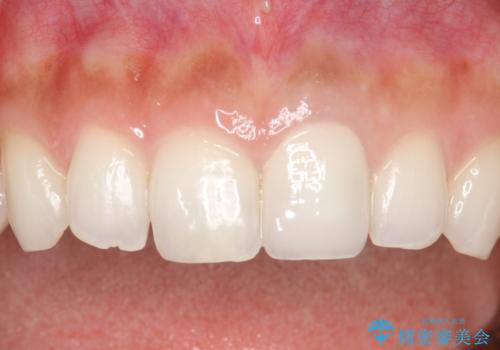

前歯のかぶせ物の色があっていない オールセラミック治療

- 以前装着された前歯のかぶせ物の色を変えたいとのことで来院されました。

土台からの再治療を行い、オールセラミッククラウンを装着する治療計画としました。

保険適用のかぶせ物は天然の歯のような色見を表現するのは難しいといえます。

自然な歯をご希望な場合、金属を使わないオールセラミックがおすすめです。